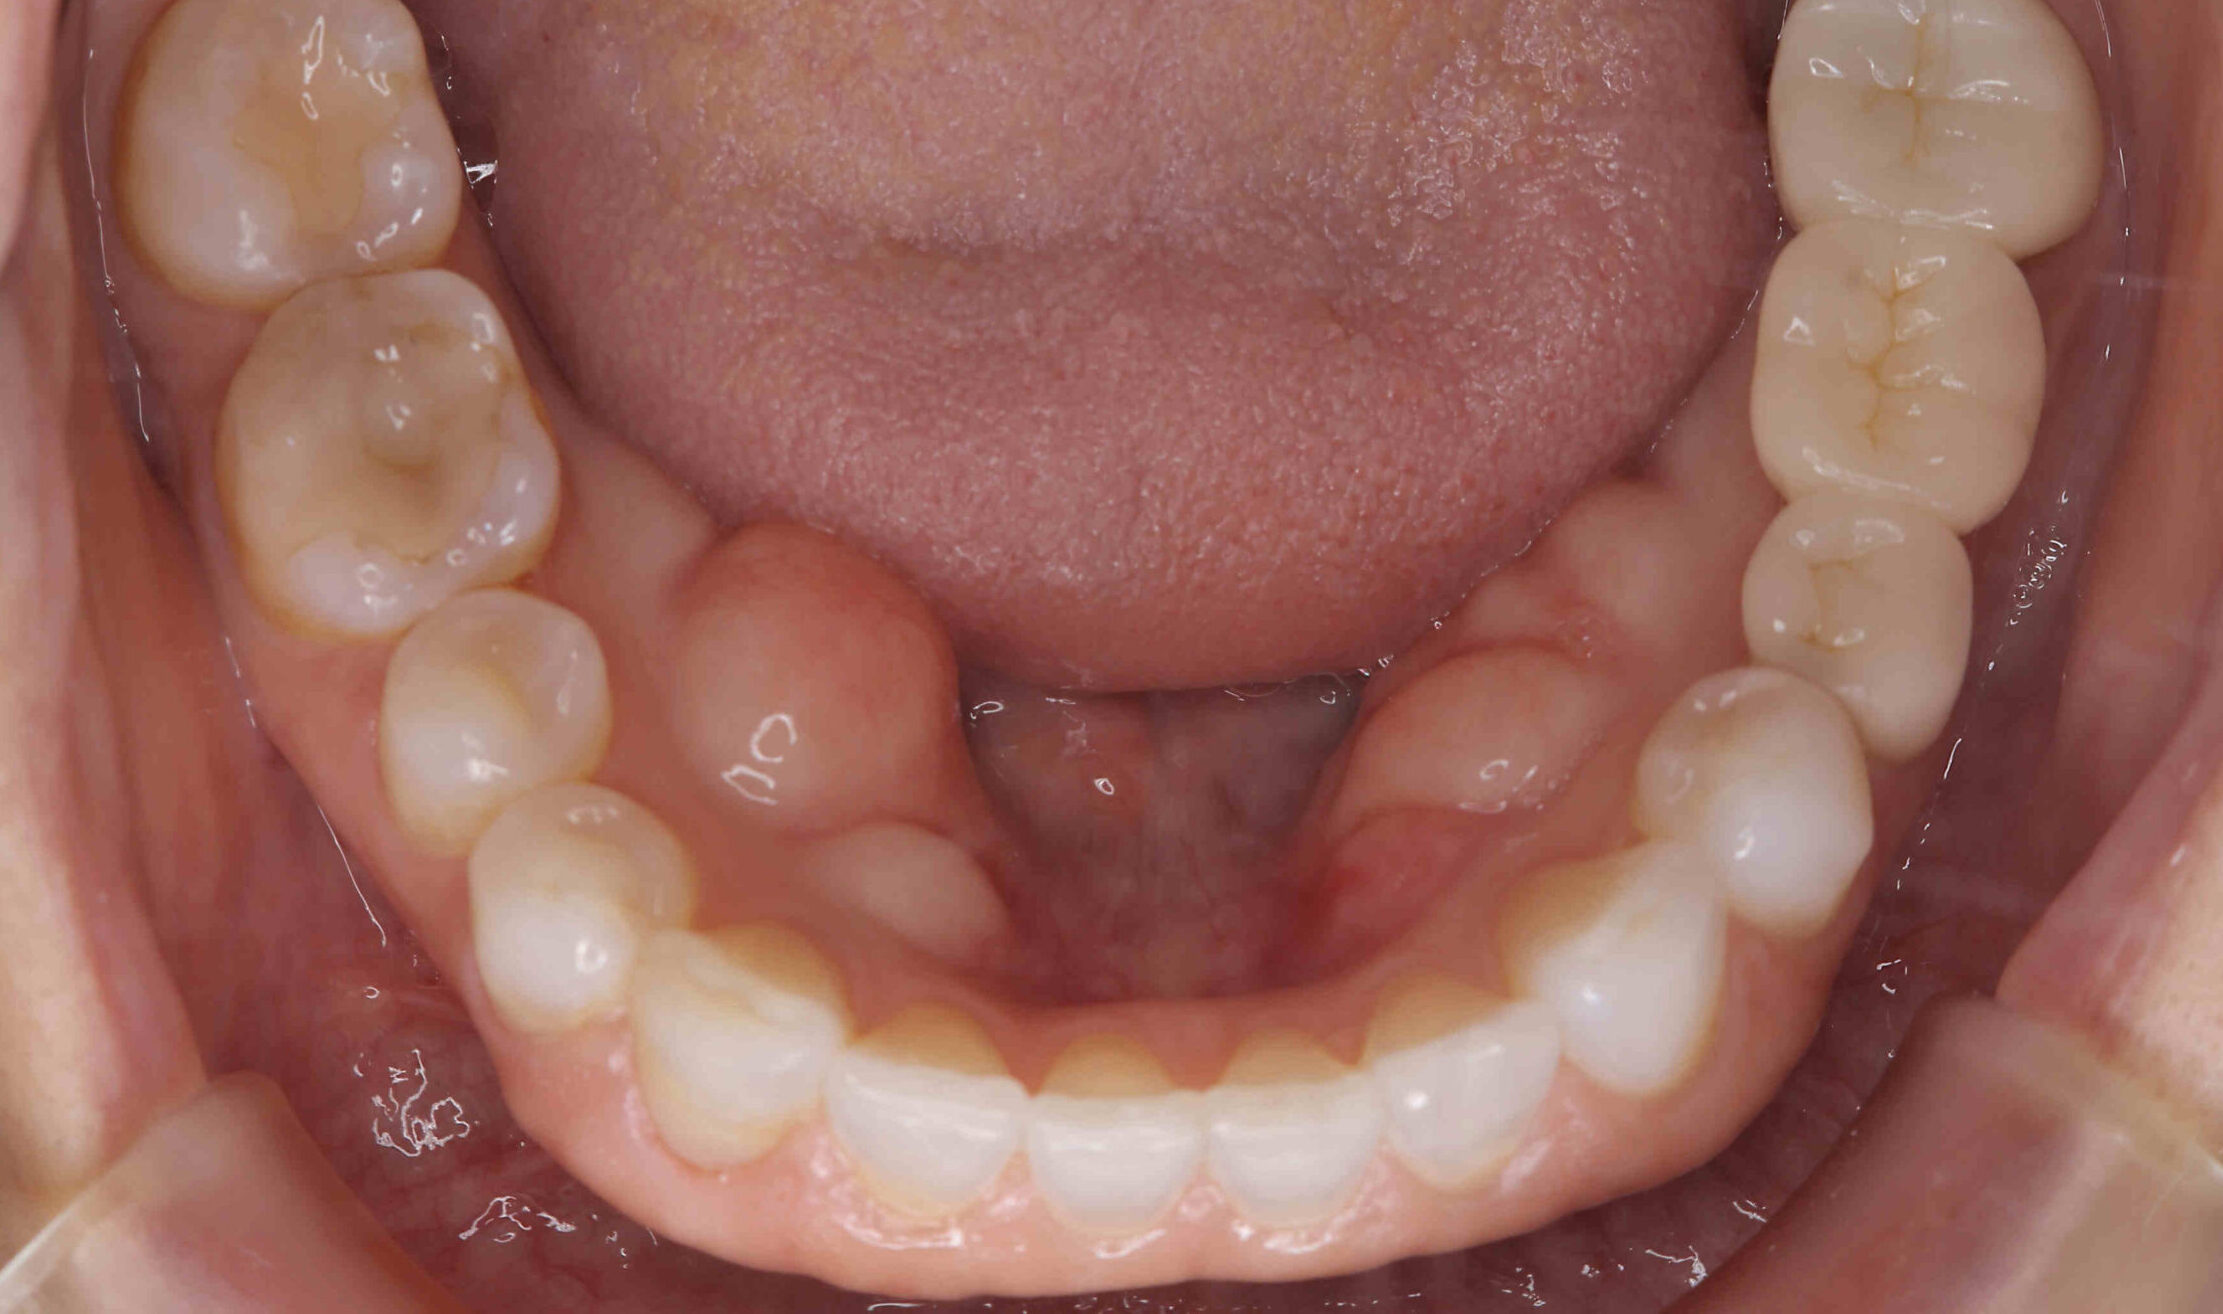

元々咬む筋力や食いしばり・歯ぎしりが非常に強く、『フレアーアウト』(前歯の歯並びが前方に放射状に倒れていく現象)によって「出っ歯」や「すきっ歯」の状態になっていました。

今回はご希望のマウスピース矯正で、食いしばりや歯ぎしりによる歯の破折やすり減りを予防しながら、歯と歯の隙間が広がって傾斜した前歯を元の位置に戻しました。

元々入っていた臼歯のブリッジは治療せず、そのままの位置で矯正を行うことを希望されたため、正中(上顎と下顎の中心線)を合わせることは難しいですが、美しい歯列と口元へ仕上がりました!